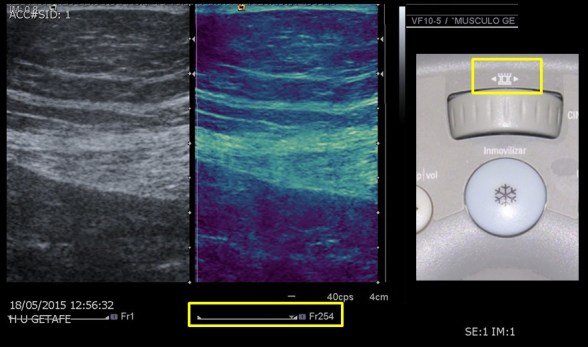

Suele tener un aspecto principal en la botonera, suele ser más grande y llamativo, estará centrado o ligeramente tirado a la derecha, cerca siempre del trackball. Como vemos en las tres imágenes anteriores de tres marcas diferentes.

En la imagen vemos dos rectángulos amarillos. En el superior a la derecha es el del icono del cine que es la rueda que está justo debajo, integrado en la consola, justo superior al botón azul de congelar o inmovilizar la imagen. Repito, en esta marca, en otras, es una función asumida por el trackball.

Abajo y central, otro rectángulo que marca una serie de imágenes o frames (acostumbraros a esta terminología) y que marca un Fr254, que quiere decir que se ha escogido la imagen 254 de todas las que habían sido guardadas en la serie, que en este caso estaría en torno a 300 imágenes…